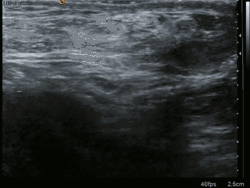

Medical imaging

A physician may diagnose an inguinal hernia, as well as the type, from medical history and physical examination.[11] For confirmation or in uncertain cases, medical ultrasonography is the first choice of imaging, because it can both detect the hernia and evaluate its changes with for example pressure, standing and Valsalva maneuver.[12]

Ultrasound image of inguinal hernia. Moving intestines in inguinal canal with respiration.